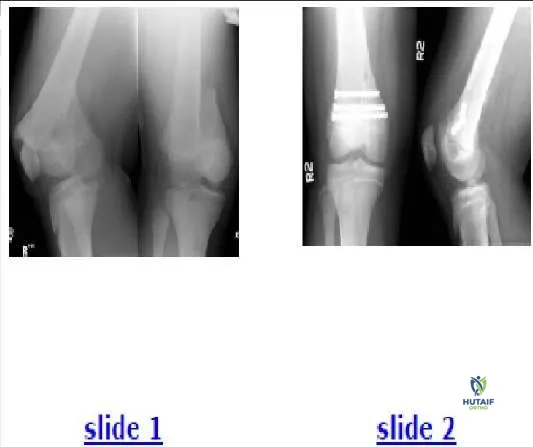

Question 15:

A 70-year-old man complains of severe, burning pain in both calves after he ambulates approximately one block. He denies significant back pain. He has long-standing, insulin-dependent diabetes mellitus and a history of coronary artery disease. The patient has smoked two packs of cigarettes each day for more than 30 years. Based upon the patientâ s history, magnetic resonance image (MRI) (Slide 1), and computed tomography (CT)-myelogram (Slide 2) available for your review, what is the correct diagnosis in this patient:

Options:

- Lumbar metastatic disease

- Lumbar spinal stenosis

- Lumbar herniated disk

- Degenerative lumbar spondylolisthesis

- Ankylosing spondylitis

Correct Answer: Lumbar spinal stenosis

Explanation:

There is no evidence of lumbar metastases in this patient. The C T- myelogram shows compression arising posterior to the thecal sac, making a disk herniation less likely. Similarly, there is no evidence of a lumbar disk herniation on MRI. The patientâ s sagittal alignment is well maintained, with no spondylolisthesis evident. Ankylosing spondylitis generally presents in younger patients, and the classic radiographic finding of spontaneous arthrodesis is not present.